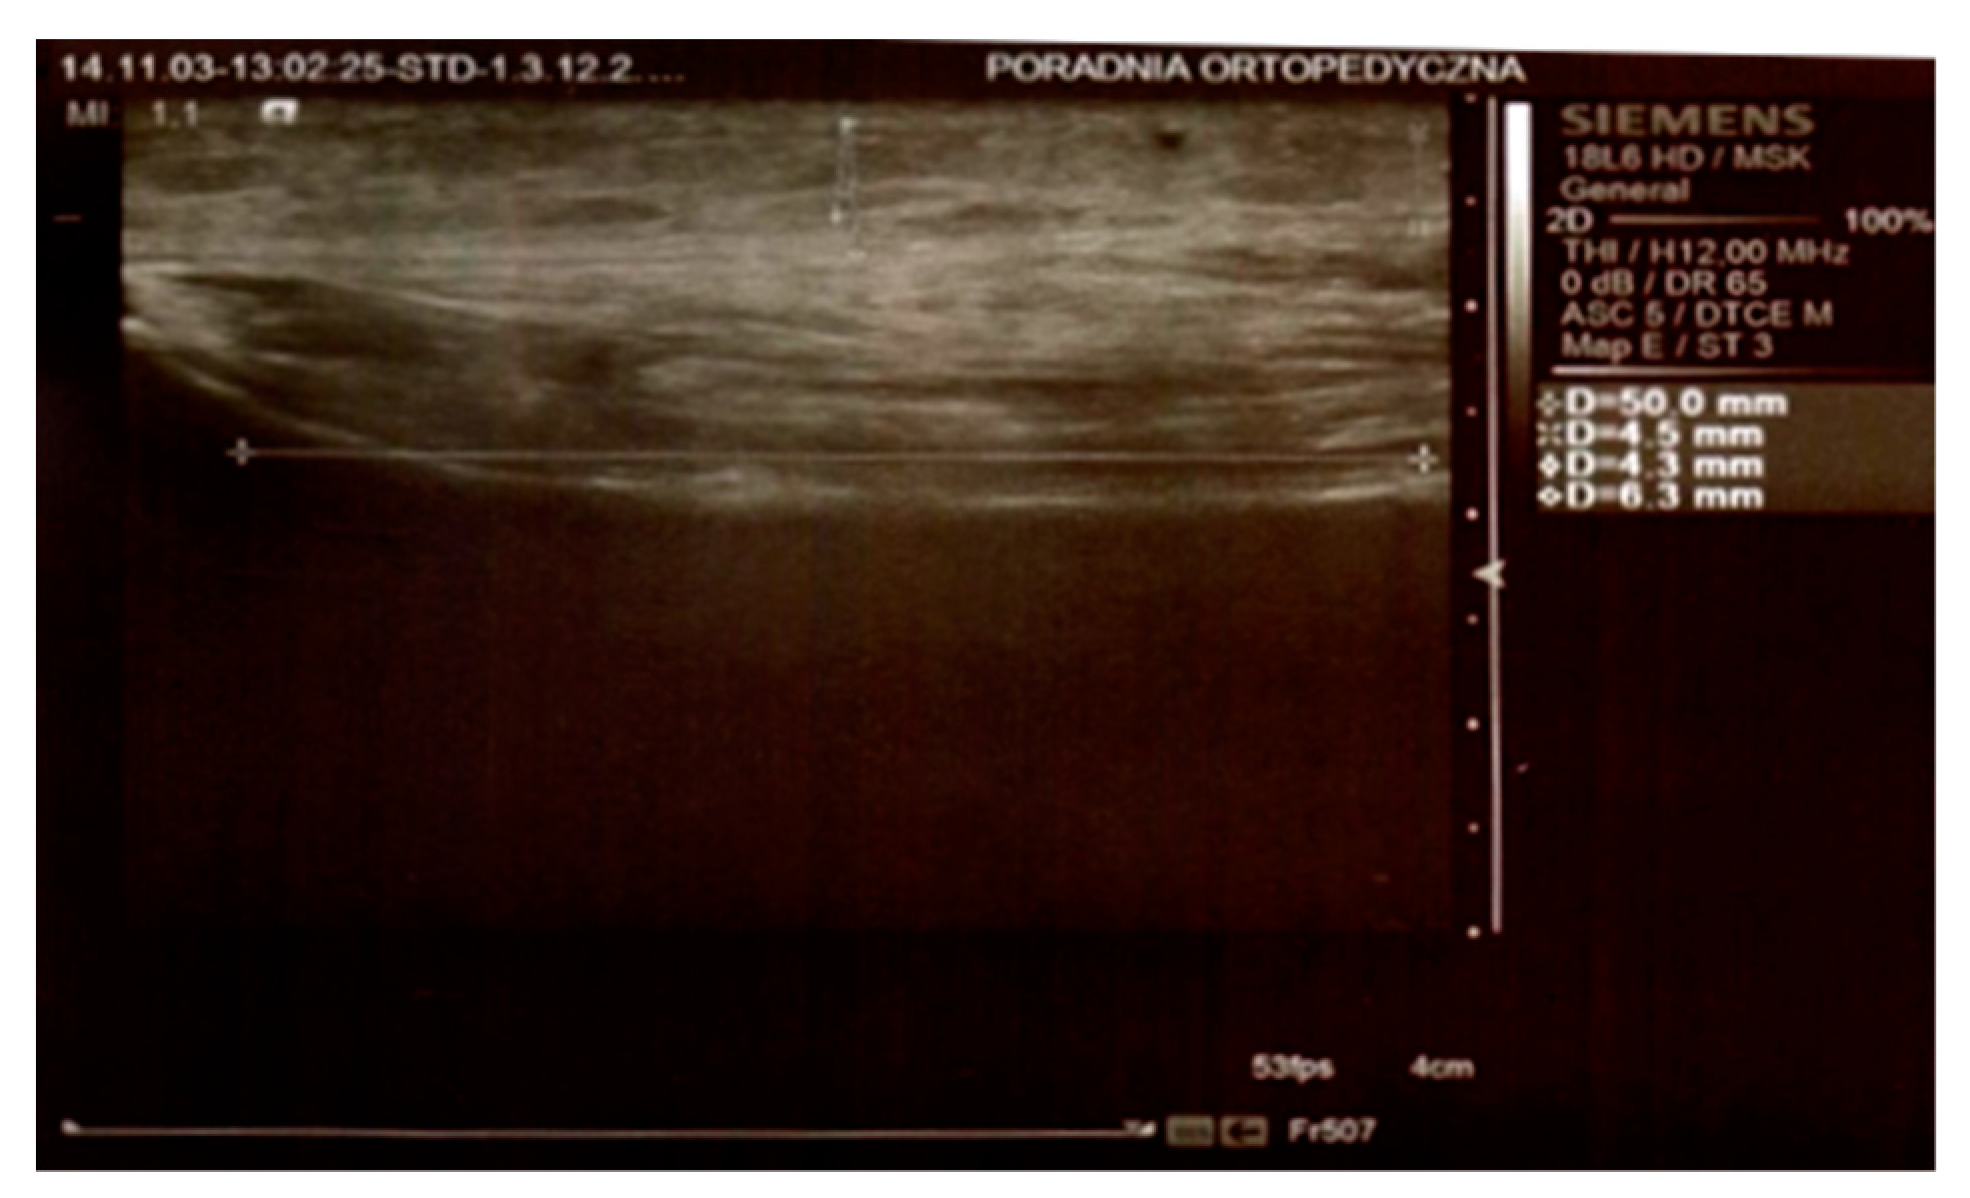

In both groups, on day 3 and 8 after the surgery, the thickness of the swelling was determined by an ultrasound scan by means of Simens ACUSON S2000 HELX EVOLUTION with a 18L6 HD linear head. The parameters were measured at the level of the top of the head of the fibula, 25 mm below the neck of the fibula, and 50 mm below the neck of the fibula on the longitudinal axis of the limb (Figure 1 and Figure 2).

Figure 2. Ultrasound scan. Measurements 25 mm below the neck of the fibula and 50 mm below the neck of the fibula.